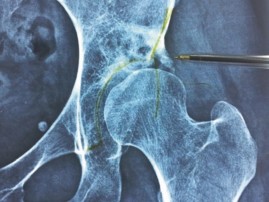

Revision THA Acetabulum: Overcoming Paprosky IIIA & Metallosis

Revision THA Acetabulum Paprosky Type IIIA. ARMD with Metallosis with Severe Periacetabular Osteolysis and Co…